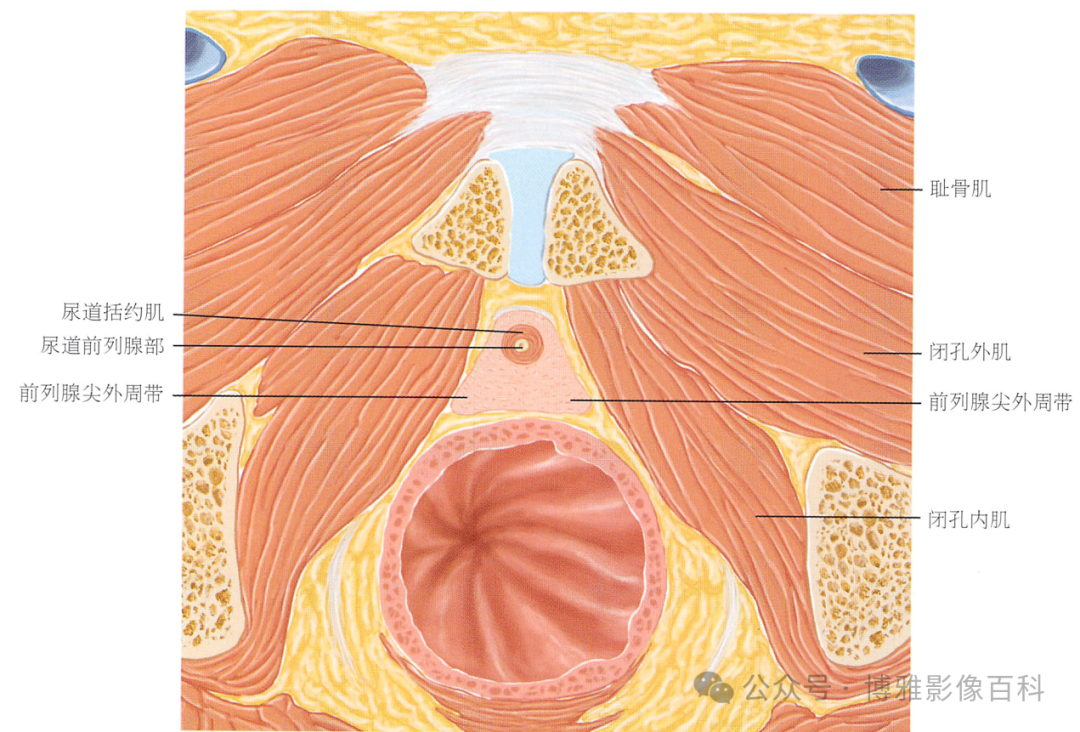

MR 解剖学

前列腺良性增生患者的轴向T2 图像,其他方面正常。外周带是一薄层均匀的高信号,边界清晰连续性的低信号包膜。移行带通常表现为不均匀中等信号,病灶被边界清楚的BPH良性前列腺增生结节所取代。精囊具有均匀T2高信号。未见淋巴结肿大。